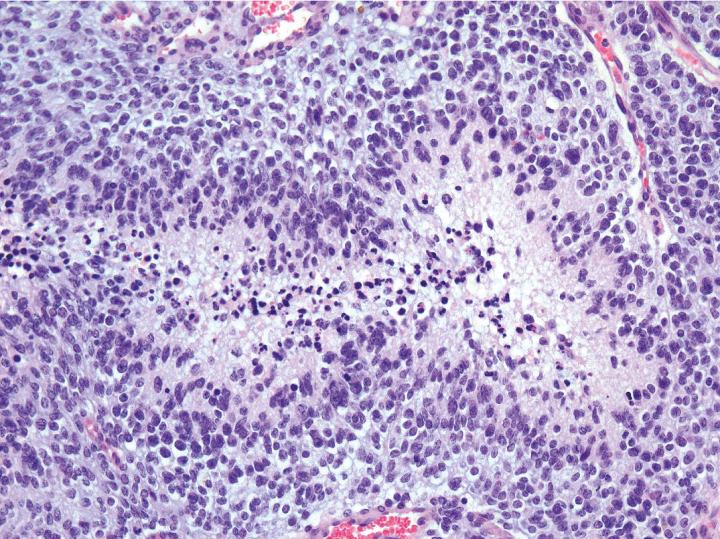

A group of researchers at the Spanish National Cancer Research Centre (CNIO) have identified a protein called RanBP6 as a new regulator of EGFR. In a paper published in Nature Communications they show how silencing of RanBP6 promoted glioma growth, by upregulating EGFR expression. Moreover, reconstitution of RanBP6 in a mouse xenograft model leads to reduction in tumor growth. Authors state that these findings might have "important clinical implications".

Malignant brain tumors represent about 3% of the known cancers and every year about 100,000 new cases are diagnosed worldwide. Glioblastoma is the most common and lethal primary central nervous system tumour in the adults. A decade of studies has underlined the complexity of the glioma genome, however, the functional significance of the vast majority of the genetic alterations remains elusive.

Focal deletions of the RanBP6 locus were found in a subset of glioblastoma patients and silencing of RanBP6 promoted glioma growth in glioma mouse model, by upregulating EGFR expression. Moreover, reconstitution of RanBP6 in human glioma cell lines that lack its expression lead to reduction in tumor growth in a xenograft mouse model.